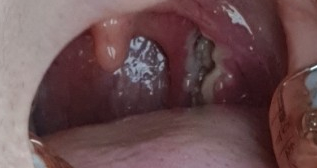

미리 예약을 해서 아침 일찍 첫 번째 타임에 받기로 했어요!입원실에서 기다리는 비포 편도를 찍어봤는데 양쪽에 포도 열매처럼 보이는 게 편도입니다.너무 지겨워요.정말 진짜 편도는 어른이 되어서 사라져야 하지만 나처럼 남아있는 사람도 꽤 있습니다.모르고 살면 괜찮지만 잦은 편도염에 시달리거나 하면 편도염이 커져 불편해집니다.저는 목이 항상 아프고 조금 아픈 느낌이 들었습니다.

싫어서 작게 올립니다!하얀 골짜기가 끼어서 불에 탄 부분이 가끔 보입니다.비포랑 비교해보니 목이 많이 넓어졌어요.근데 생각보다 많이 제거된 것 같지 않은 느낌이었어요. ㅎㅎㅎ